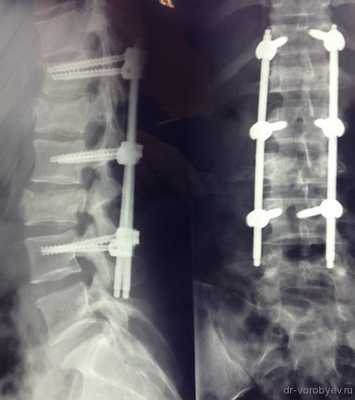

Рентген послеоперационной перкутанной ТПФ у пациентки с множественными переломами позвоночника